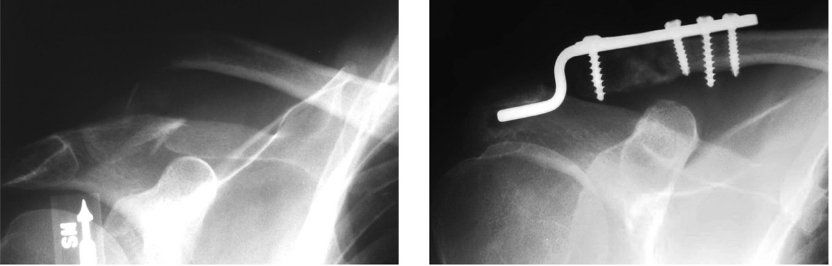

钩钢板用于锁骨远端骨折固定